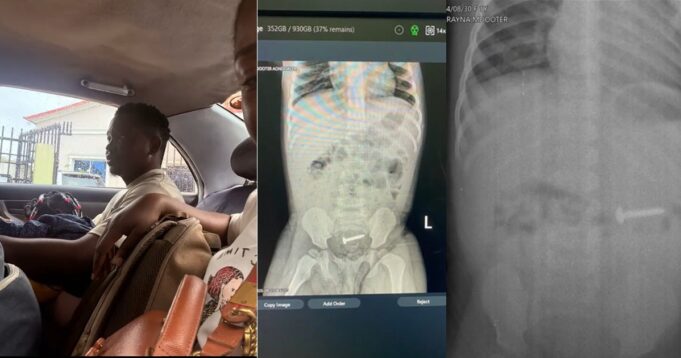

A mother has shared a miraculous story about her one-year-old daughter who swallowed a nail just a week after celebrating her first birthday.

In her post, the emotional mother revealed that doctors had initially prepared the little girl for surgery after confirming that the nail was lodged in her system. The thought of such a delicate procedure on a baby left her anxious and fearful.

But just a few hours later, what seemed like a nightmare turned into a miracle. The mother joyfully shared that her daughter passed the nail naturally through her stool before surgery could even commence.

@simply_bamike I once had a patient (an 8 year old girl) who swallowed nail but didn’t tell her parents. I’m not sure if it was because she forgot or she was afraid. But she started having breathing difficulties and her parents though it was asthma for like a week… she had a chest X-ray done but for some reasons the nail wasn’t visible in the first x-ray …. It was after the first week was referred to my unit and a repeat X-ray was done , which eventually revealed that she had swallowed a nail…… I believe training a child is not something you can do with just your own wisdom because it can really be a lot